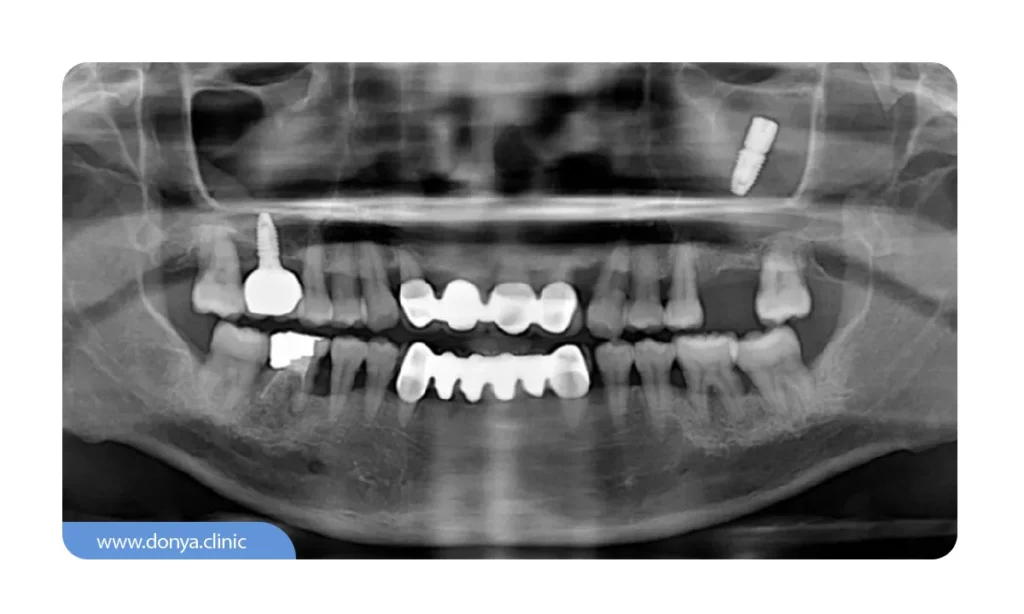

ایمپلنت دندان در داخل استخوان فک قرار می گیرد و یک پروتز دندان که شبیه تاج دندان طبیعی شما است در بالای آن چسبانده می شود. این پروتز را می توان با توجه به اندازه دهان و رنگ دندان های شما سفارشی کرد تا از سایر دندان های شما قابل تشخیص نباشد.